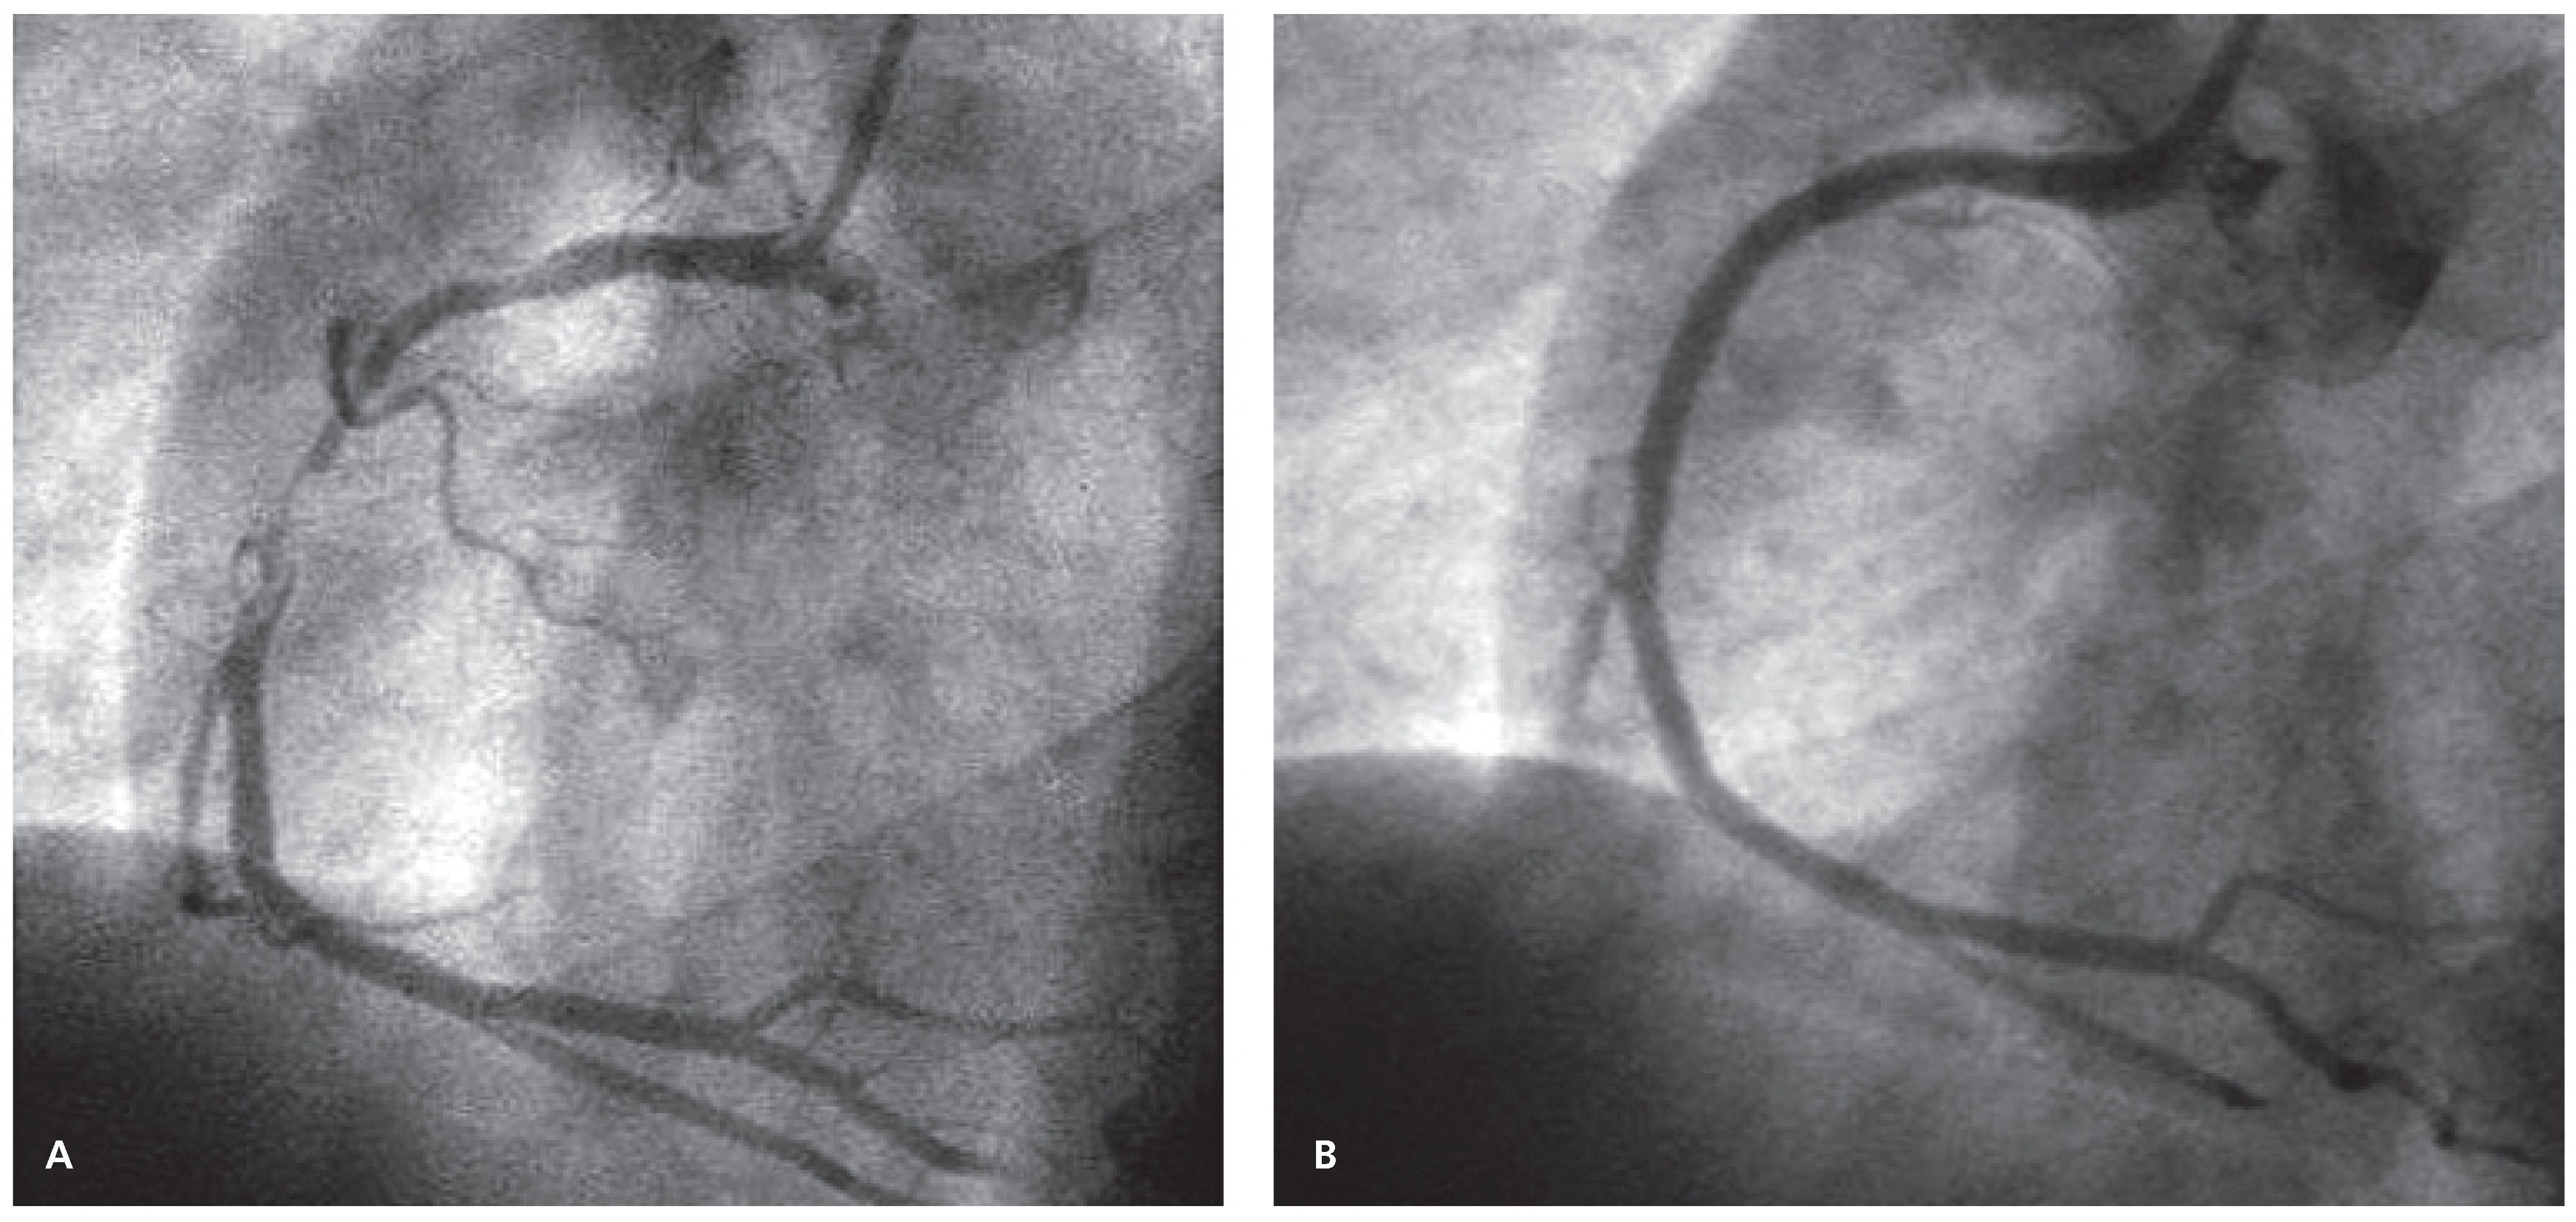

Acute Stent Thrombosis Due to Absence Without Leave (AWOL)

Case report